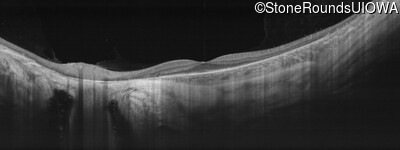

Age at visit: 30 years

This 30 year old man has had some difficulty seeing in dim light for the past few years.